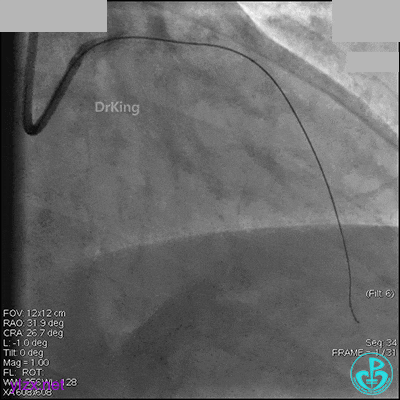

AL 1.0指引导管到位,简单短时尝试导丝不能顺利通过前降支或回旋支病变。改变策略处理右冠脉病变,计划植入2枚支架。AL指引导管到位,Sion blue导丝到达右冠脉远端。导丝通过后1.5mm及2.5mm球囊14~16atm充分扩张中段病变。